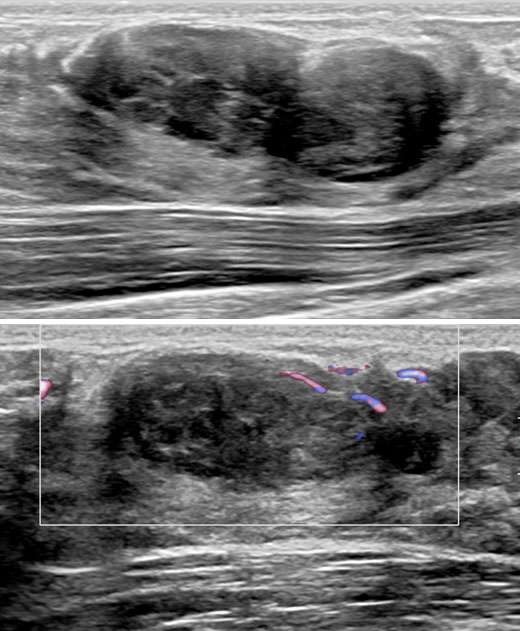

The patient underwent a diagnostic mammogram which revealed extremely dense breasts and an oval mass with circumscribed and obscured margins seen in the right breast at 9 o’clock at anterior depth (Figure 1). Targeted sonographic images were subsequently obtained which revealed a hypoechoic vascular oval mass with circumscribed margins measuring 24 x 10 x 34 mm seen in the right breast at 9 o'clock located 3 centimeters from the nipple (Figure 2). Given the patient’s medical history these findings were given BIRADS-4A and an ultrasound biopsy was recommended.

Successful ultrasound guided core needle biopsy was performed and pathology revealed a fibroepithelial lesion consistent with benign fibroadenoma. There was no evidence of atypia or malignancy.